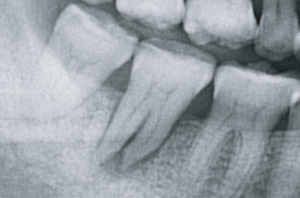

歯は通常、成人であれば28本(上下の親知らずを含めると32本)、上顎(あご)と下顎(あご)の歯が噛み合ってお互いの機能しています。理想的な咬み合わせは上顎1本に対し、下顎2本が咬み合う「一歯対二歯咬合」という状態です(図1)。

図1:一歯対二歯咬合(理想的な臼歯の位置関係)